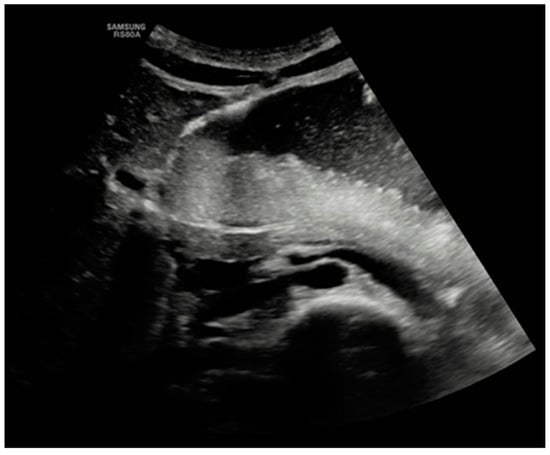

| Case index | Acute | Weight loss, Vomiting | 5 months | Upper gastrointestinal endoscopy | ||||